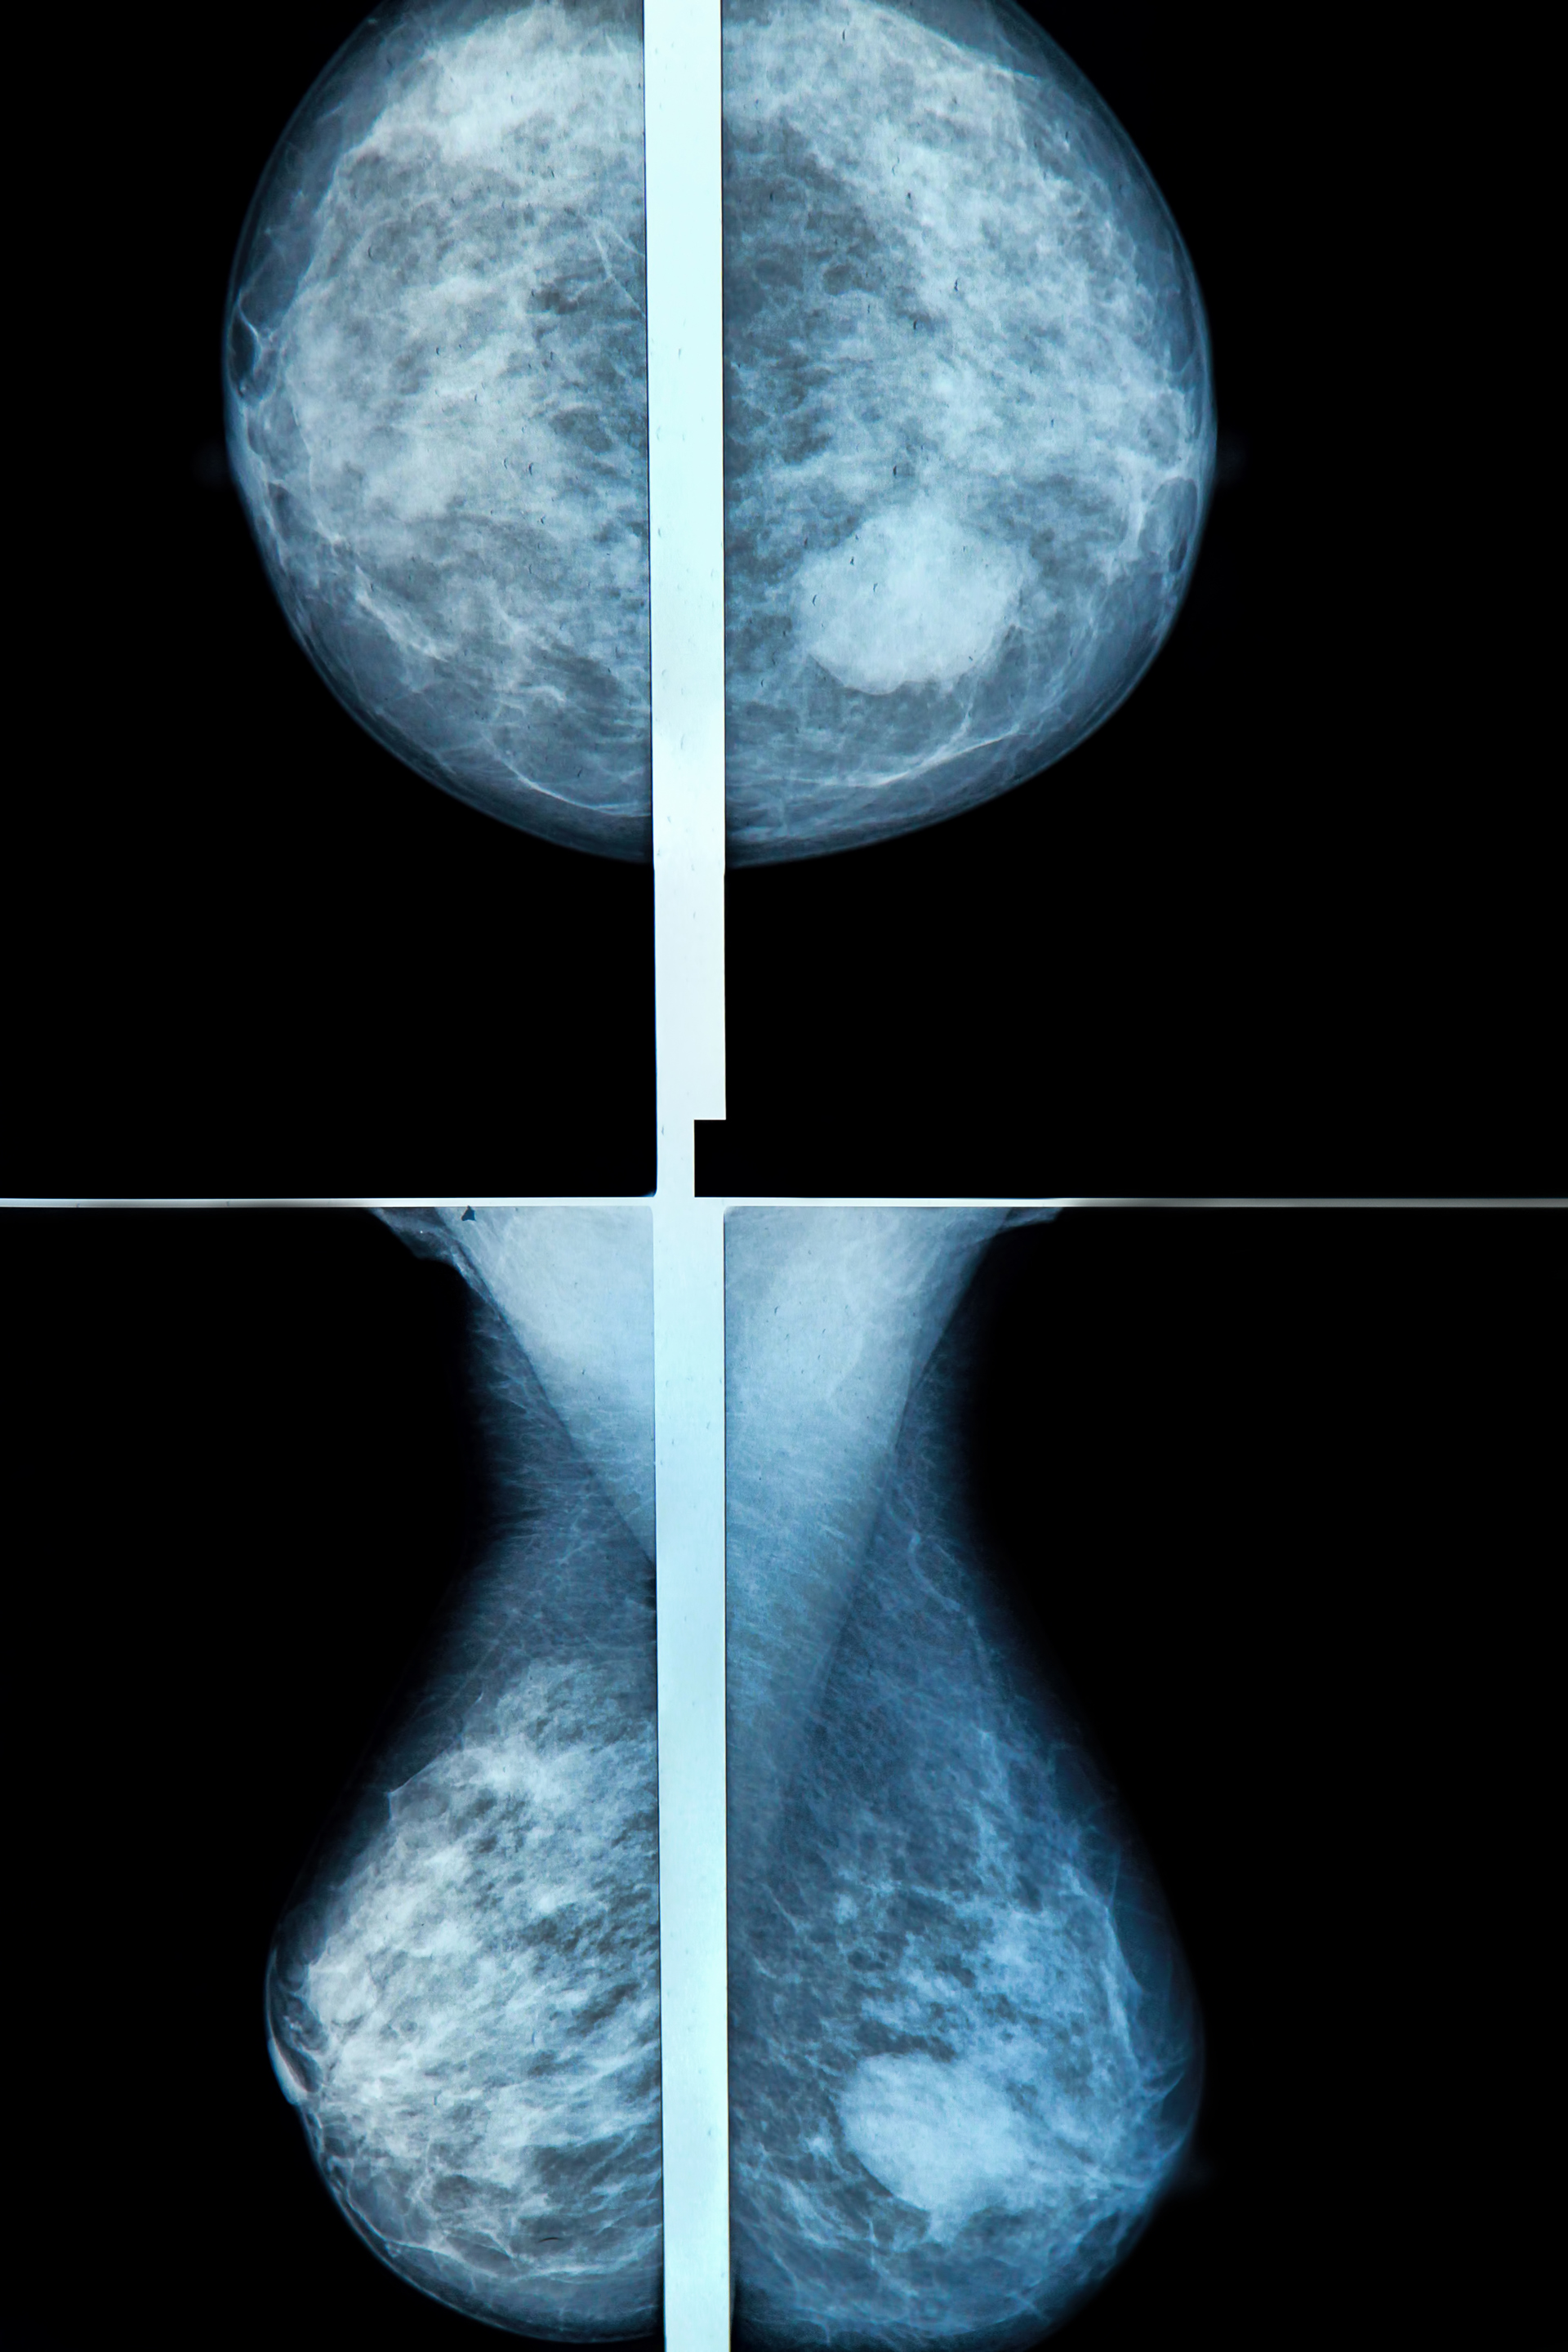

Abstract: KI som hjelpemiddel i mammografiscreening har vært lovende i mange år. Hvor står vi i dag? Er KI-CAD til å stole på? Kan det implementeres? Hva er de største utfordringene?

Abstract: Kunstig intelligens (KI) til bruk i tyding av screeningundersøkelser i Mammografiprogrammet har potensiale til å øke nøyaktigheten og redusere radiologenes arbeidsbelastning. Radiologenes holdninger og forventninger vil ha betydning for om KI blir et viktig verktøy eller en utfordring. En kartlegging av brukerperspektivet før KI tas i bruk viser optimisme blant radiologene, men de ser også noen utfordringer.

Foredrag: KI og mammografi - Ytterpunktene i differensierende tyding mellom menneske og maskin (Håkon Lund-Hanssen)